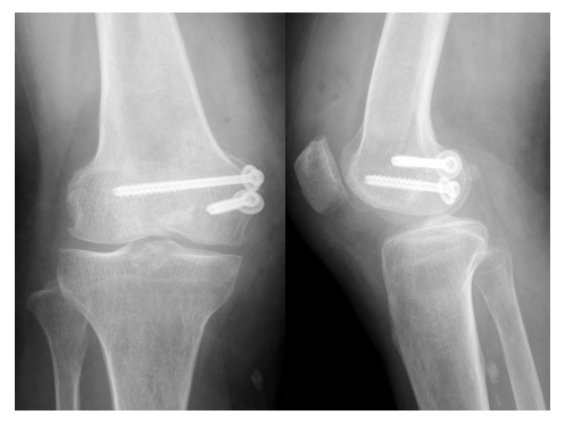

术后正侧位X线片可见,骨折对位对线良好,达到解剖复位,内固物位置良好。